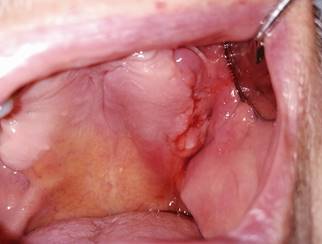

Fig. 2: Intraoral view of lesion on the left side of the maxilla with bleeding and inflammation of the surrounding tissues.

The first clinical examination found no evidence of facial asymmetries or volume increase (Fig. 1). The patient was completely edentulous and had a linear discontinuity at the mucosa of the left maxillary alveolar ridge of approximately 1 cm in diameter. It extended from the edentulous region of teeth 2.5-2.7 to the maxillary tuberosity. Clearly delimited lesion, with abundant bleeding and purulent exudate. Large edema and erythema of the surrounding soft tissues were also observed (Fig. 2). Communication with bone tissue was confirmed by probing the lesion and removing the remaining necrotic bone tissue and abundant hematic content (Fig. 3 A, B).

Given the patient’s systemic and local history, conservative management was performed after the patient signed an informed consent. Twice-a-day rinsing with 0.12% chlorhexidine was prescribed for 14 days, as well as pentoxifylline 400 mg tablets every 12 hours and tocopherol 1000 IU, 1 tablet every 24 hours. Antibiotic treatment with amoxicillin/clavulanic acid (875/125 mg) was also indicated for 14 days to treat the co-occurring infection. The patient was monitored after 14 days. We observed a decrease in purulent content and inflammation, with persisting communication with bone tissue. Antibiotic treatment was discontinued after one month. The rest of the treatment remained unchanged (PENTO protocol + topical antiseptics). The patient would be monitored every two weeks. The clinical behavior of the lesion was evaluated every two weeks. The lesion was cleaned and irrigated with topical antiseptic 0.12% chlorhexidine. The patient reported improved symptoms after six months. He reported decreased pain and bleeding in the affected area. There was evidence of healing of the affected mucosa, continuity disruption, absence of bleeding, and no inflammation of the surrounding tissue (Fig. 6). A control CBCT was ordered, which showed bone neoformation, no radiolucent areas, and bone tissue without alterations (Fig. 7). The patient continued to be monitored for two months, with no clinical or radiographic signs of MRONJ recurrence.

Mucosal healing and decreased inflammation.